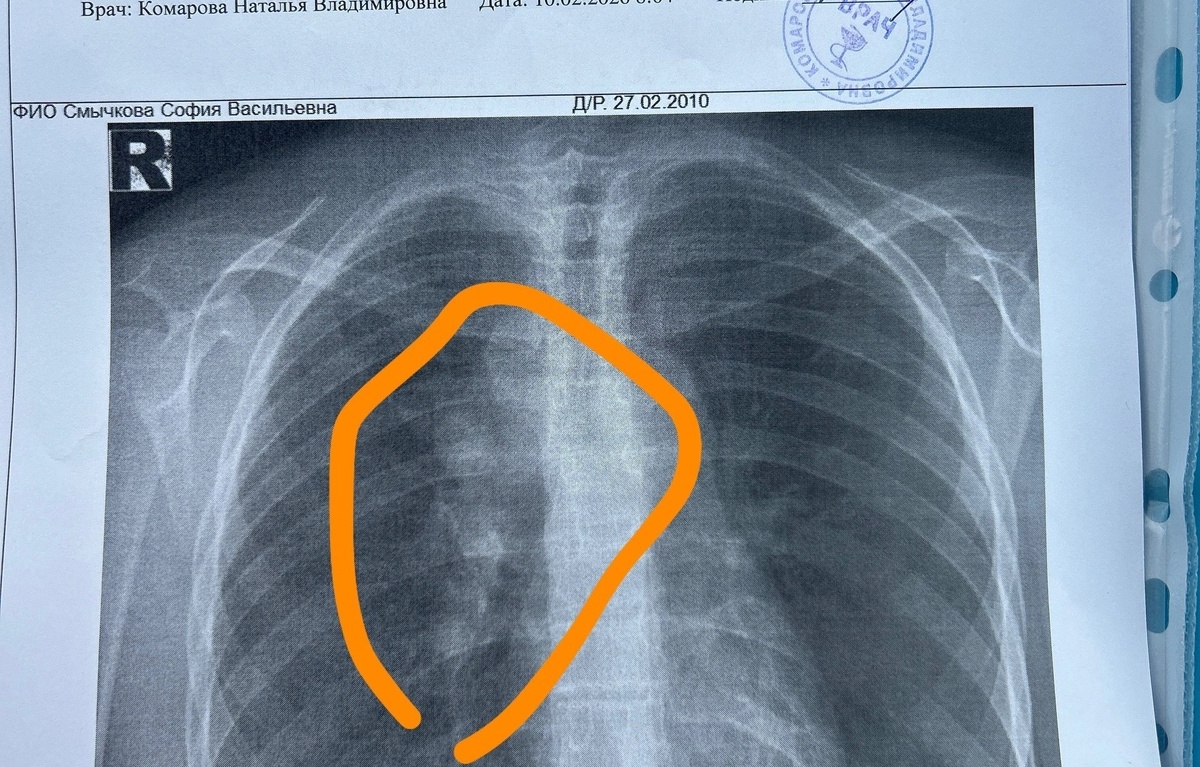

Девочке Софии из города Карабаново поставили страшный диагноз — рак: лимфогранулематоз (болезнь Ходжкина, или ходжкинская лимфома) второй стадии…